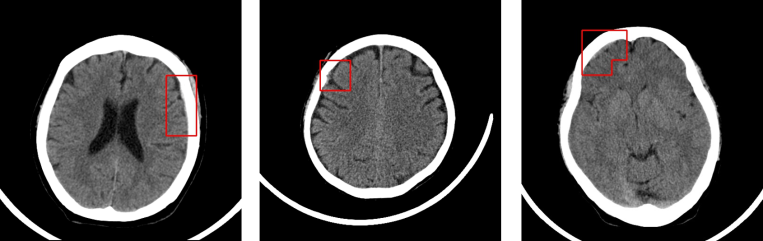

La startup taiwanesa Deep01 recauda $ 2.7 millones para su software de imágenes médicas basado en IA

Profundo01, una startup taiwanesa que desarrolla software para ayudar a los médicos a interpretar las tomografías computarizadas del cerebro con mayor rapidez, anunció hoy que ha recaudado 2,7 millones de dólares. La financiación estuvo a cargo del fabricante de PC ASUSTek. El producto de Deep01 ha obtenido la autorización de las Administraciones de Alimentos y…